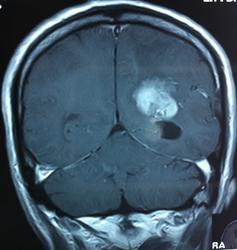

Начало вот здесь http://www.radiomed.ru/cases/kt-gms-obemnoe-obrazovanie-levoi-gemisfery-bolshogo-mozga-vnutrizheludochkovaya-meningioma. Пациент оперирован (меня сначала дезинформировали по поводу операции), перед операцией состояние ухудшилось, возникла правосторонняя гемиплегия, которая осталась и после декомпрессии. МРТ, КТ снимки и выписку предоставила супруга пациента, снимал на iphone, простите за качество, дисков с исследованиями не записывали. Надеюсь вопрос по данному случаю исчерпан.

Вот "цветочки":

T1+C

И Вы считаете, что эта опухоль имеет интравентрикулярную локализацию?

Изначально по КТ я так предпологал, а теперь на 100% уверен, разве МРТ это не показало? Гистологически - менингиома, опухоль мозговой оболочки. Покажите, пожалуйста, образование где-нибудь прилежит к костям, где есть мозговая оболочка? Я не вижу, зато отчетливо вижу в левом боковом желудочке из оболочек сосудистого сплетения. Что вас еще смущает? По-моему, предостаточно фактов, чтобы развеять все сомнения.

Мне видится так. Иначе в данной локализации просто неоткуда расти оболочечной опухоли. На контрольной КТ, после декомпрессии, когда срединные структуры стали действительно срединны, правое обызвествленное сосудистое сплетение видно отчетливо, а левое, где оно? Ведь если бы образование компремировало, то после операции, когда часть мозга пролабировало в трепанационное отверстие мы бы увидели и левое сосудистое сплетение, но оно интимно связано с образованием и даже "потянулось" за ним в сторону декомпрессионного отверстия, потому что это и есть "росток" откуда выросла опухоль.